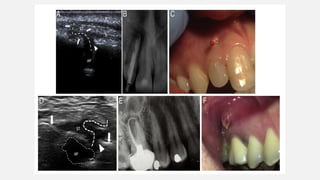

Elisabetta Cotti etal (2020)  Ultrasound real-time examination is a promising tool to detect and trace noninvasively sinus tracts of endodontic origin.  It produces a direct image rather than one obtained with a gutta- percha cone inserted into the tract. The vascular reaction within and around the tract can be also observed by the 3D rendering and the color and power Doppler implementation.

• 68.

 10 patientswho had a lesion of apical periodontitis (AP) and Sinus tract and 10 patients in the control group with AP without an Sinus tract recruited in 2 endodontic practices.  They also traced the pattern of the Sinus tracts with a computer program.  The images were then submitted to 2 calibrated and blinded observers who were asked to describe the presence of AP and Sinus tract and to trace it with the same program.  The data obtained were compared with the clinical and radiographic diagnosis of Sinus tract. Methology